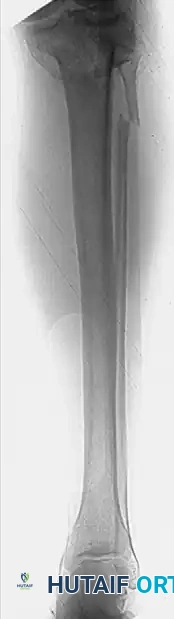

Standard radiographic evaluation includes anteroposterior (AP), lateral, and oblique views of the knee.

Surgical Warning: The upper tibial articular surface normally slopes posteriorly at an angle of 10 to 15 degrees. Therefore, a standard AP radiograph may obscure articular step-offs. An AP radiograph with the beam angled caudally 10 to 15 degrees (the "plateau view") is essential to provide a tangential view of the articular surface and accurately assess depression.

CT scanning with sagittal and coronal reconstructions is the gold standard for preoperative planning. Standard radiographs consistently underestimate the degree of articular depression and comminution. Assessment of the exact size, location, and depth of depressed articular fragments is often only possible with CT. It is common for the initial fracture classification based on plain films to be upgraded to a more complex type once the CT scan is reviewed, fundamentally altering the surgical approach and implant selection.